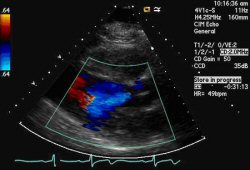

Parasternal long-axis view demonstrating aortic regurgitation jet

From the collections of Dr Sanjeev Wasson and Dr Nishant Kalra; used with permission